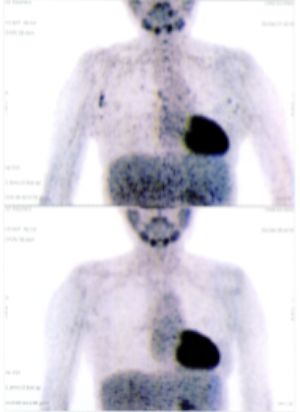

Below are some of the cases, from more than 80 cases we have treated so far with good results. When reading the PET/CT scans, the picture on the left is before treatment, and the picture on the right is after treatment. The intensity of black represents the activity of the cancer, but some black areas are not cancer: brain, heart, radioactive urine in bladder. For the heart, the intensity of black depends on the number of hours of fasting: if more than 10 hours, the heart is not even black, but if fasting is less than 6 hours, it is very black. The intensity of black in the brain can be variable in different scans depending on the brain activity at the time of the scan. The intensity of black in the radioactive urine can also be variable due to the hydration of patients and the time of injection of diuretic.

CASE NO: 31 (LUNG CANCER WITH BRAIN METASTASES)

A 40+ woman with lung cancer and brain metastases failed all treatment including radiotherapy and chemotherapy. She cannot walk. After a few treatment, the left lung cancer is gone, and all the brain metastases are gone. She is starting to walk again. One set of pictures shows the left lung cancer, and the other set of pictures show the brain: on top is BEFORE TREATMENT, bottom is AFTER TREATMENT.

CASE NO: 31 AFTER TREATMENT